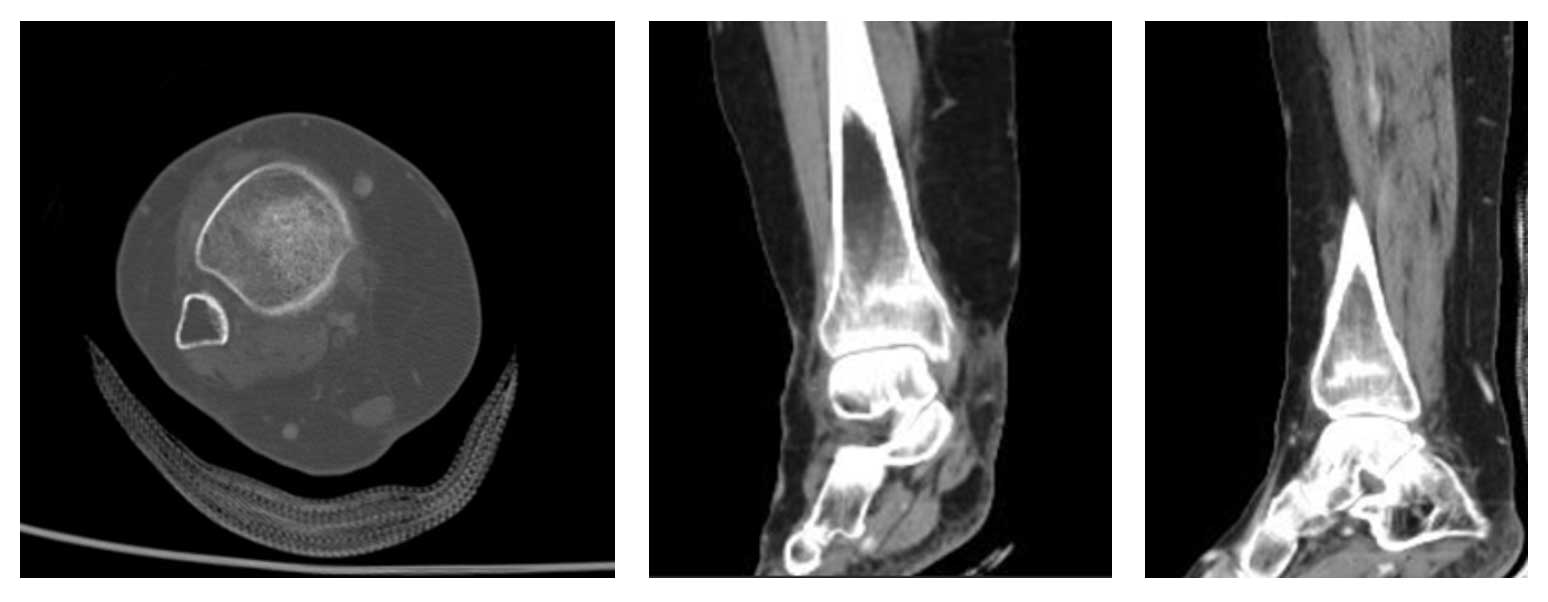

Kadın hasta, ayak bileği çevresinde ağrı ve şişlik şikayetleriyle başvurdu. Yapılan radyolojik tetkikler ve biyopsi sonucunda distal tibia yerleşimli osteosarkom tanısı konuldu. Taramalarında metastaz saptanmadı ve cerrahi tedavi planlandı.

Ameliyat Öncesi: Tomografide sklerotik lezyon ve periost reaksiyonu görülmekte.